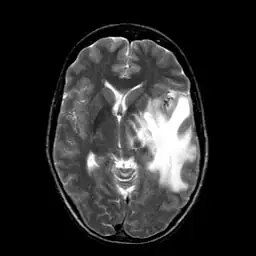

I am currently working on translating Matlab version active contour to OpenCV. It seems that OpenCV has its own version of active contour but deprecated then. I am curious about how different between this version with Matlab version. So I did a comparison experiment. Given a MRI brain image and an initial boundary , I applied both Matlab and OpenCV version active contour to segment the white matter in brain.

For both Matlab and OpenCV, I choose gradient(edge) method of active contour. I then labeled the results on the image. The red curve is initial boundary while the green curve is final boundary.

I attached the original image and mask in case someone wants to repeat the test.